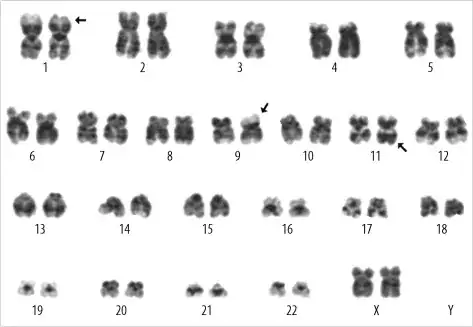

Many species (including humans) have two sets of each chromosome. If you add the other chromosome in the picture, you would see a pair of chromosome. One chromosome of the pair is said to be homologous to the other one. Below is a cladogram during the metaphase of a human (I let you figure out the sex) showing each pair of chromosome.

Sister chromatids are identical (except for mutation during the last chromosomal replication). Homologous chromosomes are similar but not identical. Crossover occurs in between chromatids of homologous chromosomes.

There are 23 pairs of chromosomes, that is 46 chromosomes. Your picture shows only one chromosome per pair, that is your picture shows only 23 chromosomes. In other words, your picture shows the haploid genome and not the diploid genome.